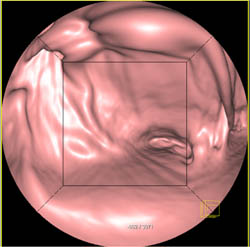

Antral Cancer